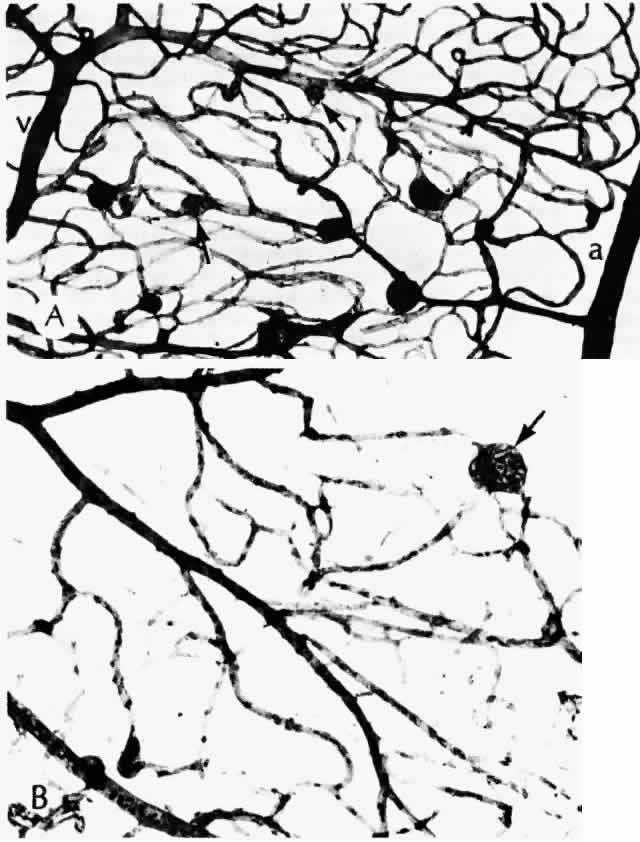

Histologically, new vessels develop between the retinal surface and the posterior surface of the formed vitreous (Fig. 12). With NVE, there is a demonstrable break through the internal limiting membrane (Fig. 13).20 Early-developing new vessels have lumina even at the proliferating tips.53 Active new vessels have endothelial cells and pericytes, with fenestrations. Morphologically, fenestrations are areas ranging from 40 to 80 nm in diameter where the cell membranes are focally fused, and are normal findings in capillaries outside of the retina and brain. They allow increased permeability and are responsible for the diffuse leakage of fluorescein seen from new vessels on angiography. Inactive or “ghost” new vessels are acellular, having lost both endothelium and pericytes.39 With time, fibrous tissue develops and accompanies the new vessels. The vessels themselves may leak and bleed into the vitreous, leading to visual loss.

Fig. 12. Neovascularization at the disc with fibrous proliferation. The fibrovascular membrane overlies the internal limiting membrane, which is wrinkled (arrows). The retinal detachment is artifactual. (PAS, × 19.5)

Fig. 13. Neovascularization away from the disc. The fibrous tissue has contracted, imparting a triangular shape to the membrane. Active new vessels are present throughout. The dark folds are artifactual. (H&E, × 31.25)